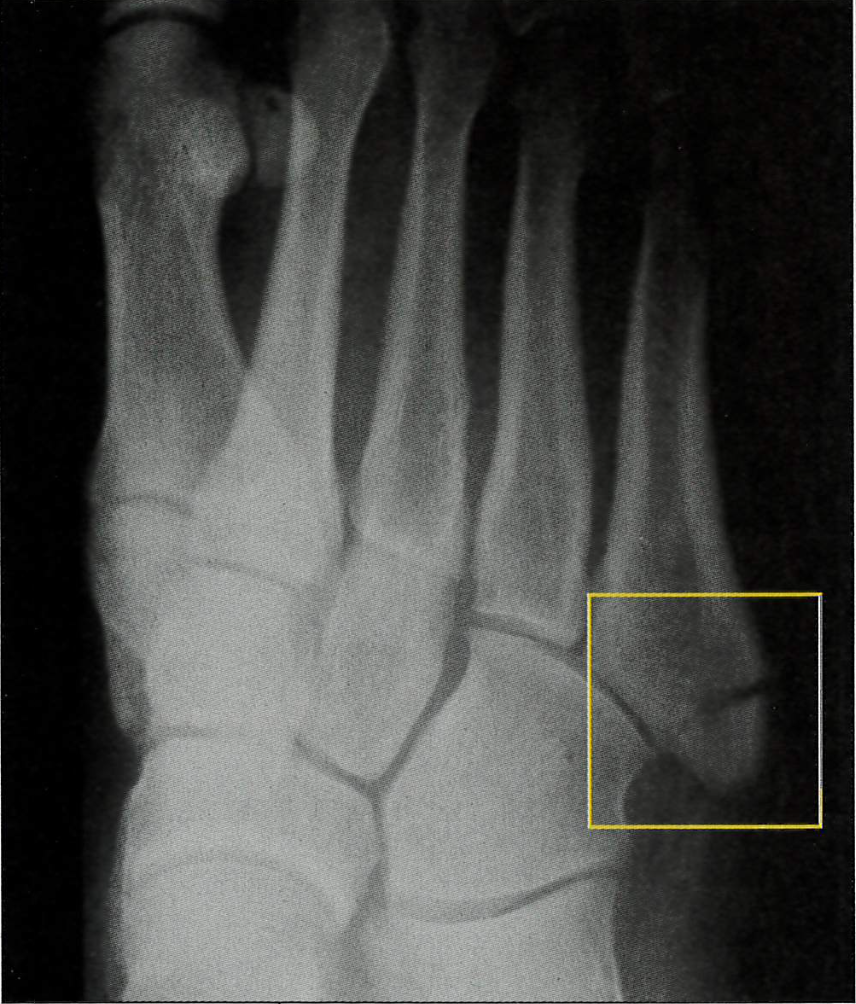

Radiographic findings. Fractures of the talar dome primarily occur on either the posterolateral or anteromedial aspect of the talar dome. Often the fracture is not visible on radiographs because of the curvature of the talar dome and because the area of the talar dome where the fracture occurs is usually not included on routine radiographs of the ankle. When the fracture is evident on radiographs, changes are located on either the lateral or medial aspect of the talar dome (Figure 5).

Management. When a fracture is evident on initial radiographs, immobilization and referral to an orthopedic specialist is warranted. Fragments of this fracture can become loose in the joint. Loose bodies in the joint can lead to episodes of sharp pain inside the ankle accompanied by a feeling that something is in the way. Because the fracture is generally not evident on radiographs, a talar dome fracture becomes the working diagnosis when the patient is slow to progress during or after a comprehensive lateral ankle sprain treatment program. For instance, if the patient has persistent pain inside the ankle with or without loose-body sensations during the program or after he returns to functional activities and follow- up radiographs are negative, the working diagnosis is a talar dome fracture and referral to an orthopedic specialist for further evaluation with a bone scan or MRI is warranted.

It is important to be able to distinguish a talar dome fracture from osteochondritis dissecans, in which a portion of the talar dome loses its blood supply (Figure 6). This type of avascular necrosis usually occurs during adolescence. The resulting bony lesion may remain asymptomatic and heal uneventfully with the return of adequate blood supply to the area, or it may present with symptoms compatible with a talar dome fracture (pain inside the ankle with or without loose-body sensations). The symptoms may develop insidiously or with any acute injury to the ankle.